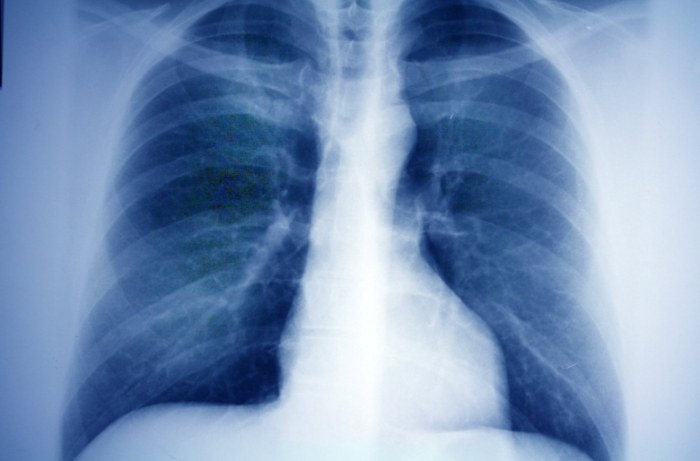

最常見的就是胸部X光片和胸部電腦斷層掃描(CT)。胸部X光相對便宜、輻射低,但有它的限制,比較小的結節或者位置刁鑽的被肋骨擋住的結節,X光可能就看不到了。現在很多健康檢查會納入低劑量電腦斷層(LDCT)篩檢早期肺癌,它的靈敏度高太多了,1-2毫米的小點點都能抓出來。很多原本X光看不到的肺結節,一做LDCT就無所遁形,這也是為什麼感覺「肺結節」變多了的原因之一。這點「肺結節知識」能幫助大家理解為何近年來診斷率提高。

肺結節,說白了就是在肺部影像上(通常是電腦斷層掃描,CT)看到的一個小點點、小團塊。聽我說,這個小點的定義非常重要:它必須是圓的或類圓的,邊界相對清晰,而且直徑小於或等於3公分。如果大於3公分,我們就不叫它肺結節了,我們稱之為「腫塊」,性質和處理方式會很不一樣。所以下次聽到肺結節,心裡要有個概念:大小是個關鍵指標。這個「肺結節知識」是理解後續所有問題的基礎。